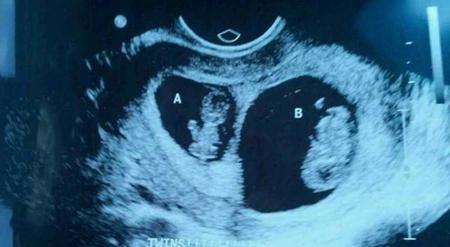

由于怀双胎会比怀单胎风险更大,因此怀双胞胎的人产检会更频繁一些。当做三维、四维彩超时,双胎孕妈咪产检的时间可能也会更长一些,因为要排除两个宝宝的畸形,自然要花费更多的时间。当然,医生还会根据孕妈咪的情况,适当增加产检的次数,以便于及时掌握两个胎儿的发育情况。